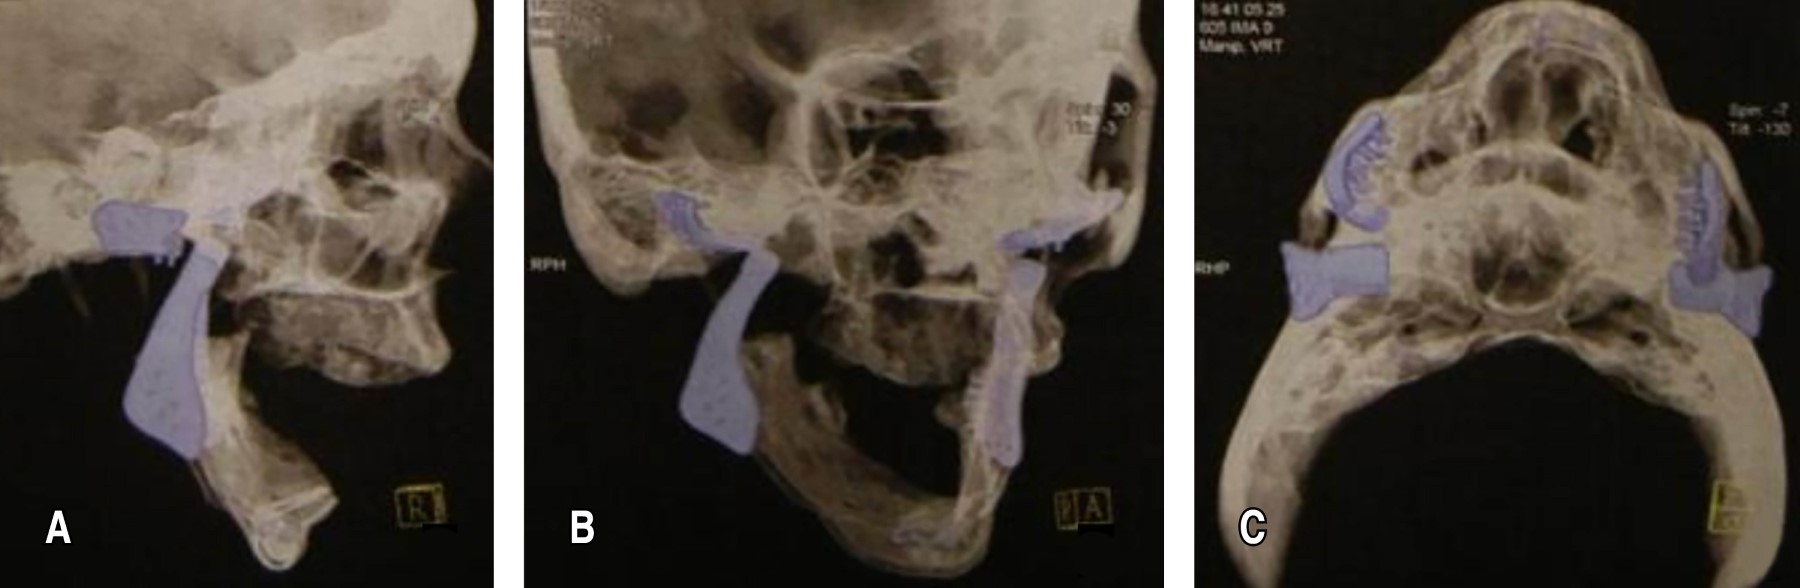

Durante la planificación quirúrgica, se analizó la opción de una prótesis personalizada de articulación temporomandibular, ya que, debido al gran avance del caso, no era posible utilizar una prótesis estándar (Figura 2). Una de las dificultades del caso fue que la paciente presentaba edéntula bimaxilar, lo que dificultaba la planificación de la relación maxilomandibular y la fijación de las prótesis, al no existir una referencia oclusal (Figura 3). La planificación se basó en los exámenes de imagen. Su fijación se realizó teniendo en cuenta la anatomía mandibular y la perfecta adaptación de la prótesis personalizada.

Figura 2

Figura 3